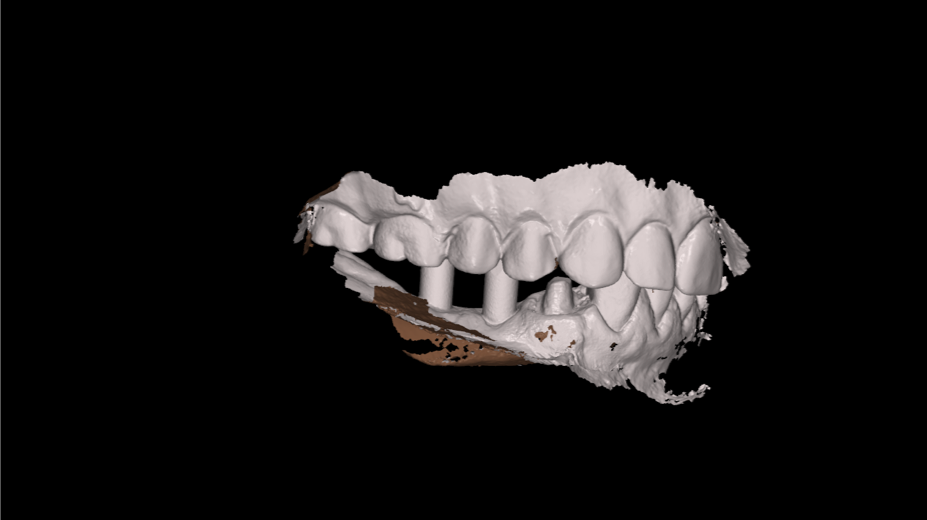

The CBCT and digital scan were placed in software to merge the two. Figure 8 shows the superimposition of the scan over the CBCT. The clinician used the volumetric data to determine implant size, depth, and position. The surgeon, dentist, and laboratory were all involved in a conference call to go through several different implants. They chose the implant size and length based on the position of the sinus, the width of the alveolus, and the appropriate position for an ideal surgical result.

Fig 8. Superimposition of digital scan over the CBCT.

Figure 8